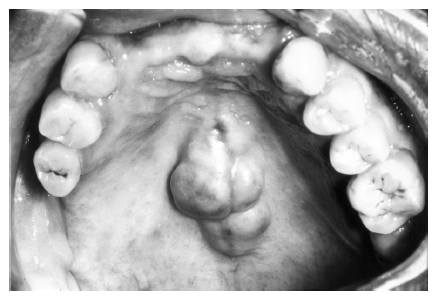

Concrescence

Concrescence represents the joining of adjacent teeth via the cementum with obliteration of the intervening periodontal ligaments. Concrescence is usually found in two teeth, rarely in three or more. The clinical appearance of the condition is shown in Figure 41 and the appearance on a radiographic image in Figure 42.

Figure 41 - Clinical Concrescence

Figure 41

Figure 42 - Radiographic Concrescence

Figure 42